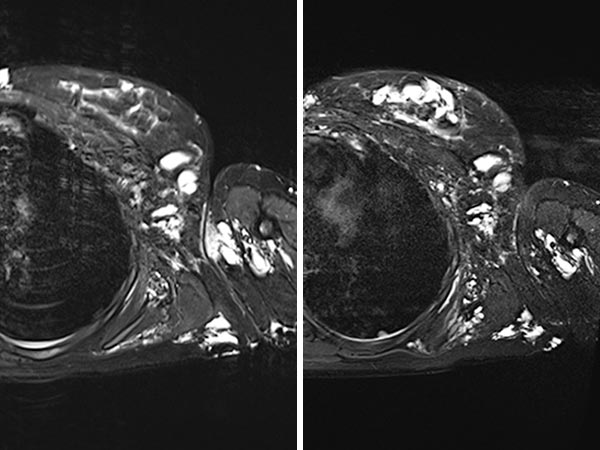

MRT (T2-Wichtung mit Fettunterdrückung; axial) vor (links) und nach (rechts) der Elektrosklerotherapie. Nur die behandelten Anteile der lymphatischen Malformation (LM) sind stark geschrumpft, die übrigen Anteile unverändert.

Gleiche MRT (T2-Wichtung mit Fettunterdrückung; jetzt koronare Rekonstruktion) vor (links) und nach (rechts) der Elektrosklerotherapie. Auch hier sieht man, dass die behandelten Anteile der lymphatischen Malformation praktisch verschlossen sind, die übrigen Anteile aber unverändert.